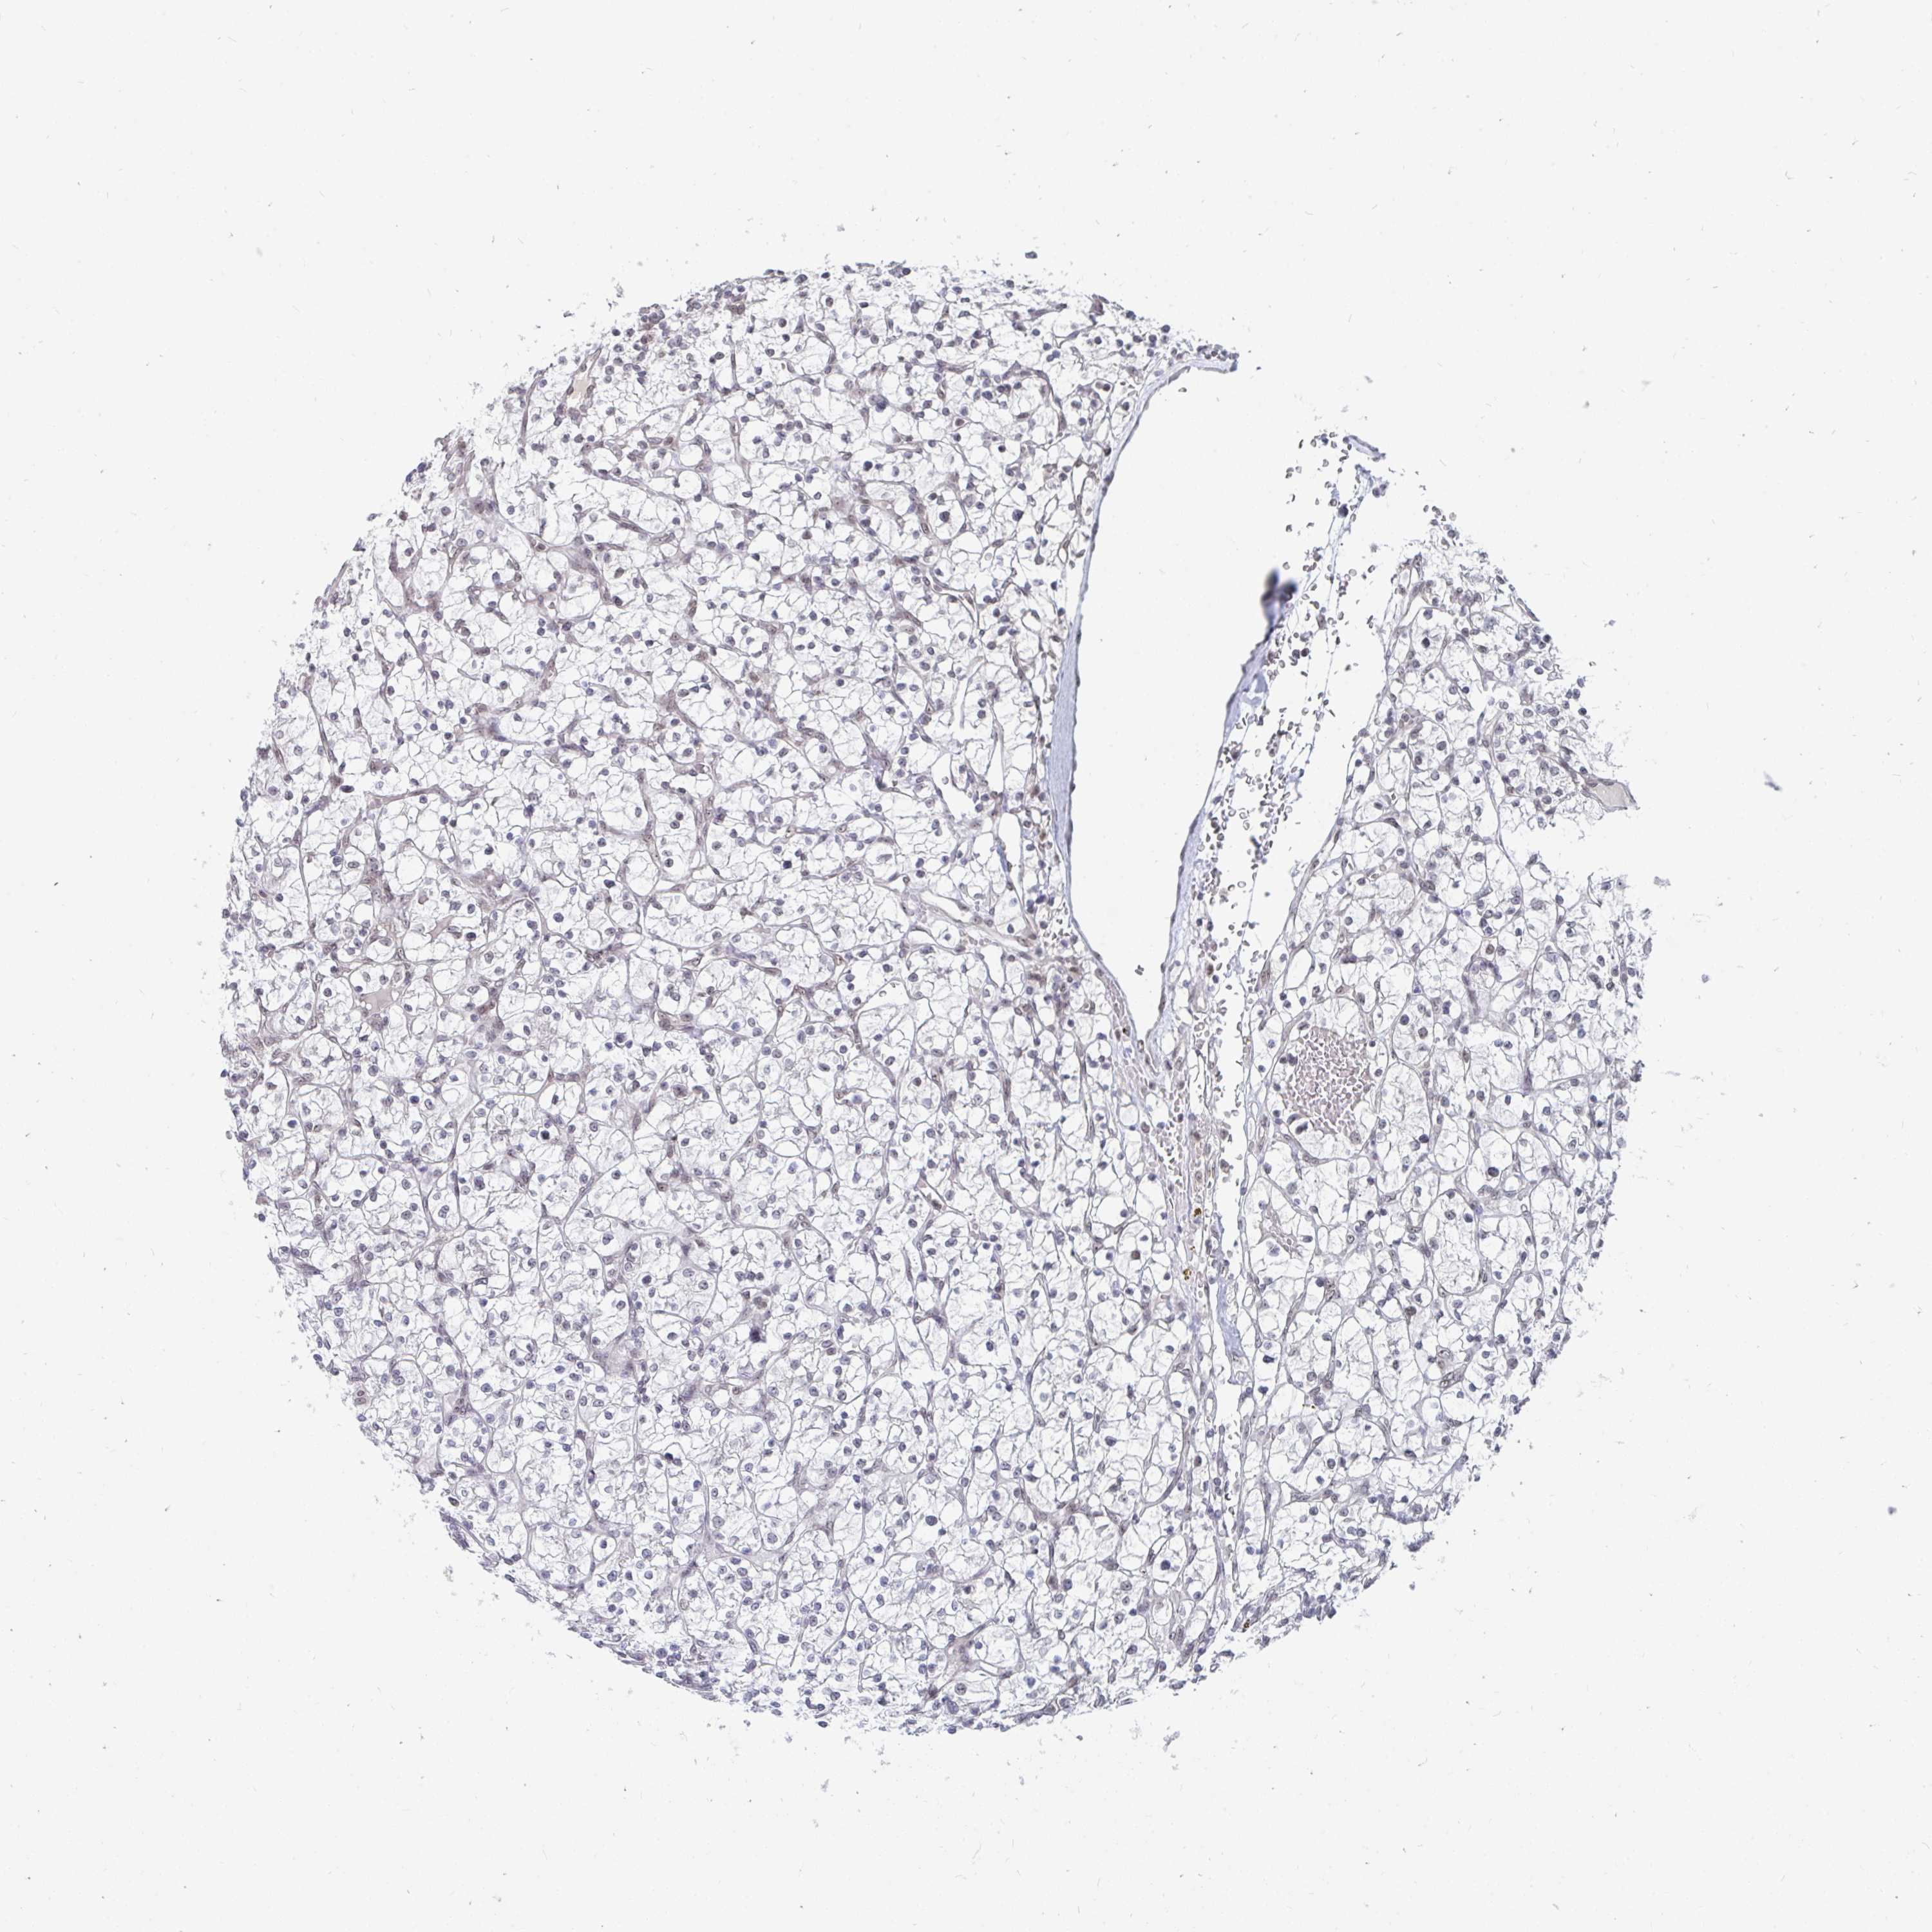

KIDNEY RENAL CLEAR CELL CARCINOMA (VALIDATION) - Interactive survival scatter ploti

The Survival Scatter plot shows the clinical status (i.e. dead or alive) for all individuals in the patient cohort, based on the same data that underlies the corresponding Kaplan-Meier plots. Patients that are alive at last time for follow-up are shown in blue and patients who have died during the study are shown in red.

The x-axis shows the expression levels (FPKM) of the investigated gene in the tumor tissue at the time of diagnosis. The y-axis shows the follow-up time after diagnosis (years). Both axes are complimented with kernel density curves demonstrating the data density over the axes. The top density plot shows the expression levels (FPKM) distribution among dead (red) and alive patients (blue). The right density plot shows the data density of the survived years of dead patients with high and low expression levels respectively, stratified using the cutoff indicated by the vertical dashed line through the Survival Scatter plot. This cutoff is automatically defined based on the FPKM cutoff that minimizes the p-score. The cutoff can be changed by dragging the vertical line or by entering a cutoff value in the square labeled "Current cut-off".

Under the Survival Scatter plot the p-score landscape (black curve; left axis) is shown together with dead median separation (red curve; right axis). Dead median separation is the difference in median mRNA expression between patients who have died with high and low expression, respectively. It is calculated as follows: median FPKM expression of dead patients with high expression - median FPKM expression of dead patients with low expression. This is intended to aid the user in visually exploring custom cutoffs and the associated p-scores and dead median separation.

Individual patient data is displayed and can be filtered by clicking on one or more of the category buttons on the top of the page. Categories describing expression level and patient information include: high, low, alive, dead, female, male and tumor stages. The scale of the x-axis can be toggled between linear and log-scale by clicking on the "x log" button. Mouse-over function shows TCGA ID, patient information and mRNA expression (FPKM) for each patient.

& Survival analysisi

Kaplan-Meier plots summarize results from analysis of correlation between mRNA expression level and patient survival. Patients were divided based on level of expression into one of the two groups "low" (under cut off) or "high" (over cut off). X-axis shows time for survival (years) and y-axis shows the probability of survival, where 1.0 corresponds to 100 percent.

TRIP12 is not prognostic in Kidney Renal Clear Cell Carcinoma (validation)

Best expression cut offi

Based on the FPKM value of each gene, patients were classified into two groups and association between prognosis (survival) and gene expression (FPKM) was examined. The best expression cut-off refers the FPKM value that yields maximal difference with regard to survival between the two groups at the lowest log-rank P-value. Best expression cut-off was selected based on survival analysis .

When clicking on this number, the vertical dashed line indicating cut-off, the interactive survival plot, and the Kaplan-Meier curve will be adjusted to show results based on the best expression cut-off.

: 77.98

P scorei

Log-rank P value for Kaplan-Meier plot showing results from analysis of correlation between mRNA expression level and patient survival.

N/A

TCGA RNA samplesi

RNA-seq data is reported as average FPKM (number Fragments Per Kilobase of exon per Million reads), generated by the The Cancer Genome Atlas (TCGA) .

Normal distribution across the dataset is visualized with box plots, shown as median and 25th and 75th percentiles. Points are displayed as outliers if they are above or below 1.5 times the interquartile range. FPKM values of the individual samples are presented next to the box plot.

Average pTPM 62.1

Number of samples 100